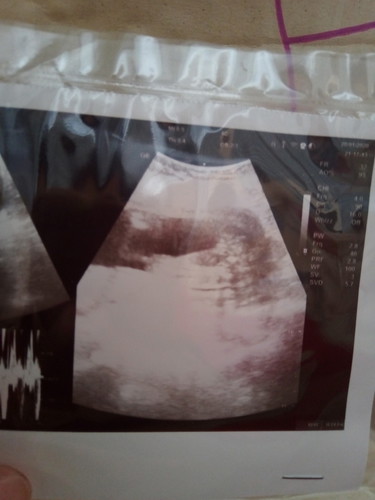

เพศลูก

เห็นหว่างขาน่าจะหญิงนะคะแม่ (แบบแม่บ้านนี้) ซาวด์แรกๆ หมอ3ท่านว่าผู้หญิง แต่แล้วจู๋มาโผล่เอาซาวด์รอบที่4ตอน35+6 หมอคนที่4ฟันธงว่าผู้ชาย

หมอบอกแค่ว่าน่าจะญ แต่แม่กลัวออกมาเปนชายคะ

น่าจะหญิงนะคะ

หมอบอกรอซาวใหม่อีกรอบคะ เขาว่าไม่เหนจู๋น่าจะญ ไว้ก่อนคะ

ลูกสาวค่ะแม่

ญ ค่ะ